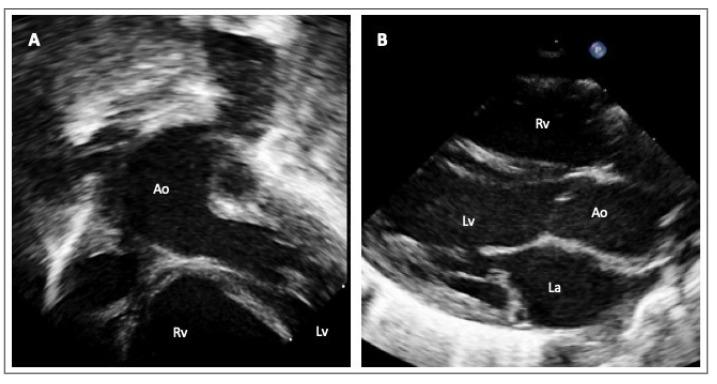

Advances in both imaging techniques and genetics have led to the recognition of a wide variety of aortic anomalies that can be grouped under the term 'hereditary thoracic aortic diseases'. The present review aims to summarize this very heterogeneous population's clinical, genetic, and imaging characteristics and to discuss the implications of the diagnosis for clinical counselling (on sports activity or pregnancy), medical therapies and surgical management.

成像技术和遗传学的进展已使人们认识到多种主动脉异常,这些异常可归类于“遗传性胸主动脉疾病”这一术语之下。本综述旨在总结这一非常异质性群体的临床、遗传和影像学特征,并讨论诊断对临床咨询(关于体育活动或妊娠)、药物治疗和手术管理的意义。